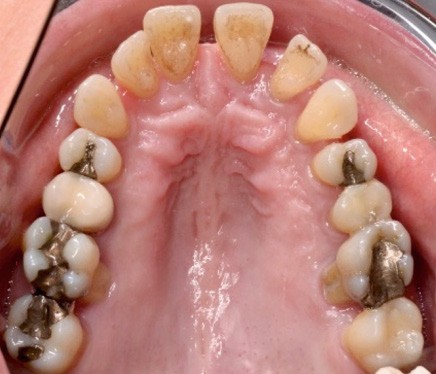

À l’examen endo-buccal (fig. 2), on note une formule dentaire complète (absence des 8) avec présence de restaurations multiples étanches, un bon contrôle de plaque et une parodontite de stade 4 grade C stabilisée [3], des récessions gingivales et des mobilités dentaires généralisées (degré 2, classification de Miller). L’arcade mandibulaire présente une courbe de spee importante avec égression du bloc incisivo-canin. Les milieux inter-incisifs sont alignés, le recouvrement est normal, le surplomb est augmenté à 3 mm et associé à des diastèmes et de la vestibulo-version des incisives maxillaires. Les relations antéro-postérieures canine et molaire sont en Classe I d’Angle.

L’analyse des moulages indique une dysharmonie dento-dentaire (indice de Bolton) par excès mandibulaire antérieur (0,7 mm).